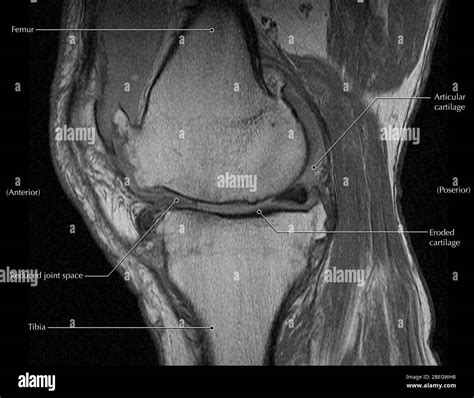

• Meniscus Damage: Identifying tears in the cartilage discs that act as shock absorbers between your shinbone and thighbone.

• Cartilage Defects: Detecting wear and tear, or osteochondral lesions, which are often indicative of osteoarthritis.

After your MRI of knee is completed, a radiologist—a physician specialized in interpreting diagnostic images—will review the scans. They will produce a detailed report outlining their findings. It is important to remember that these results must be correlated with your clinical symptoms by your referring physician. Sometimes, an MRI might show a minor tear in the meniscus that is actually asymptomatic and not the cause of your current pain.